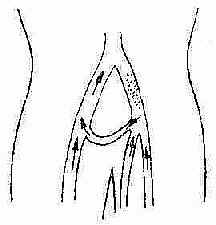

(二)中央型(腹股沟韧带近段型) 血栓形成局限于髂股静脉段,不向腹股沟韧带远段的静脉扩展,血栓很少再通,主要表现为远侧静脉回流障碍,主干静脉瓣膜和踝交通支功能未受破坏。治疗宜行大隐静脉移植转流术(图2-122)。

图2-122 大隐静脉移植转流术